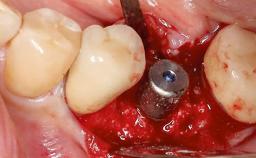

This case describes both a surgical and an anti-infective approach for the management of peri-implantitis, including treatment of the entire dentition to eliminate any deep periodontal pockets that could serve as reservoirs for bacterial re-colonization at the implant site. A 65-year-old female patient was referred to the periodontist in 2013 for assessment and management of an infection at implant 12. On examination, probing depths at implant 12 were 11 mm with suppuration and bleeding on probing.